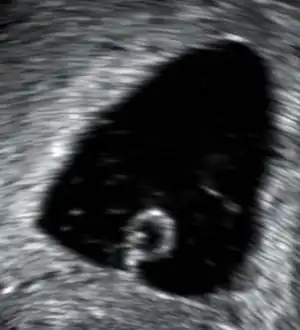

Œuf clair, cas de gestation anembryonnique conduisant inévitablement à une fausse couche.

La première cause de fausses couches[9] est une anomalie chromosomique de l'embryon, due à un problème survenu lors de la conception, quand le spermatozoïde féconde l'ovule. L'organisme de la mère finit par expulser l'embryon qui ne se développe pas normalement. L'absence de développement de l'embryon donne un œuf clair (œuf ne contenant pas d'embryon comme la photo de l'infobox). Un œuf clair est causé par une anomalie chromosomique.

• L'échographie permet de déceler un embryon mort (cœur ne battant pas), ou un œuf clair (embryon pas développé), ou de constater que l'utérus est en train de se vider ou déjà vide à la suite des saignements de fausse couche.